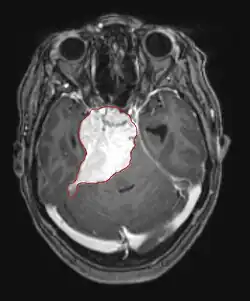

Metástases cerebrais

As metástases cerebrais são as neoplasias intracranianas mais comuns em adultos, sendo dez vezes mais comuns que os tumores cerebrais primários. Eles pisam em 20 até 40 por cento dos adultos com câncer e estão associados principalmente ao câncer de pulmão e mama e melanoma . Essas lesões resultam da disseminação de células cancerígenas pela corrente sanguínea e ocorrem mais comumente na junção da substância cinzenta e branca, onde a seção transversal dos vasos sanguíneos se altera, aprisionando embolias de células tumorais . 80 por cento das lesões ocorrem nos hemisférios cerebrais, 15 por cento no cerebelo e 5 por cento no tronco cerebral. Cerca de 80 por cento dos pacientes têm história de câncer sistêmico e 70 por cento têm múltiplas metástases cerebrais.

Avanços significativos foram feitos recentemente no diagnóstico e tratamento dessas lesões, resultando em melhora da sobrevida e controle dos sintomas. O início dos sinais e sintomas é semelhante ao de outras lesões maciças no cérebro. O método diagnóstico de escolha é a ressonância magnética com meio de contraste.

A literatura mostra resultados equivalentes para cirurgia e radiocirurgia. Este último parece ser mais conveniente, eficaz e seguro para lesões pequenas ou em regiões inacessíveis à cirurgia. A radiocirurgia é uma alternativa sensata para pacientes que não podem ser operados por razões médicas. No entanto, a cirurgia é claramente o método ideal para obter tecidos para diagnóstico e remover as lesões que causam efeito de massa. Portanto, a radiocirurgia e a cirurgia devem ser melhor consideradas como dois métodos complementares, mas diferentes a serem aplicados, dependendo da situação diferente do paciente. Por quase 50 por cento dos pacientes com uma ou duas metástases cerebrais não são candidatos à remoção cirúrgica devido à inacessibilidade das lesões, extensão da doença sistêmica ou outros fatores. Esses e outros pacientes com metástases múltiplas geralmente recebem radioterapia panencefálica como padrão de tratamento. Na verdade, chegar até quase 50 por cento deles com esta terapia uma melhora nos sintomas neurológicos e 50 até 70 por cento uma reação perceptível. A quimioterapia raramente é usada principalmente para metástases cerebrais.